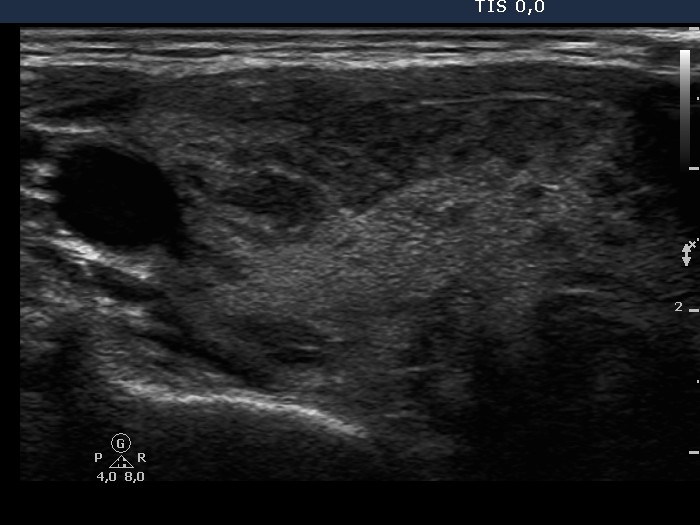

Follow-up investigation 32 months after first visit (ultrasonographic picture 1)

Patient 14 months after discontinuation of thyrostatic therapy in hyperthyroid state

Right lobe, transverse scan. The echogenicity index is around 30%.